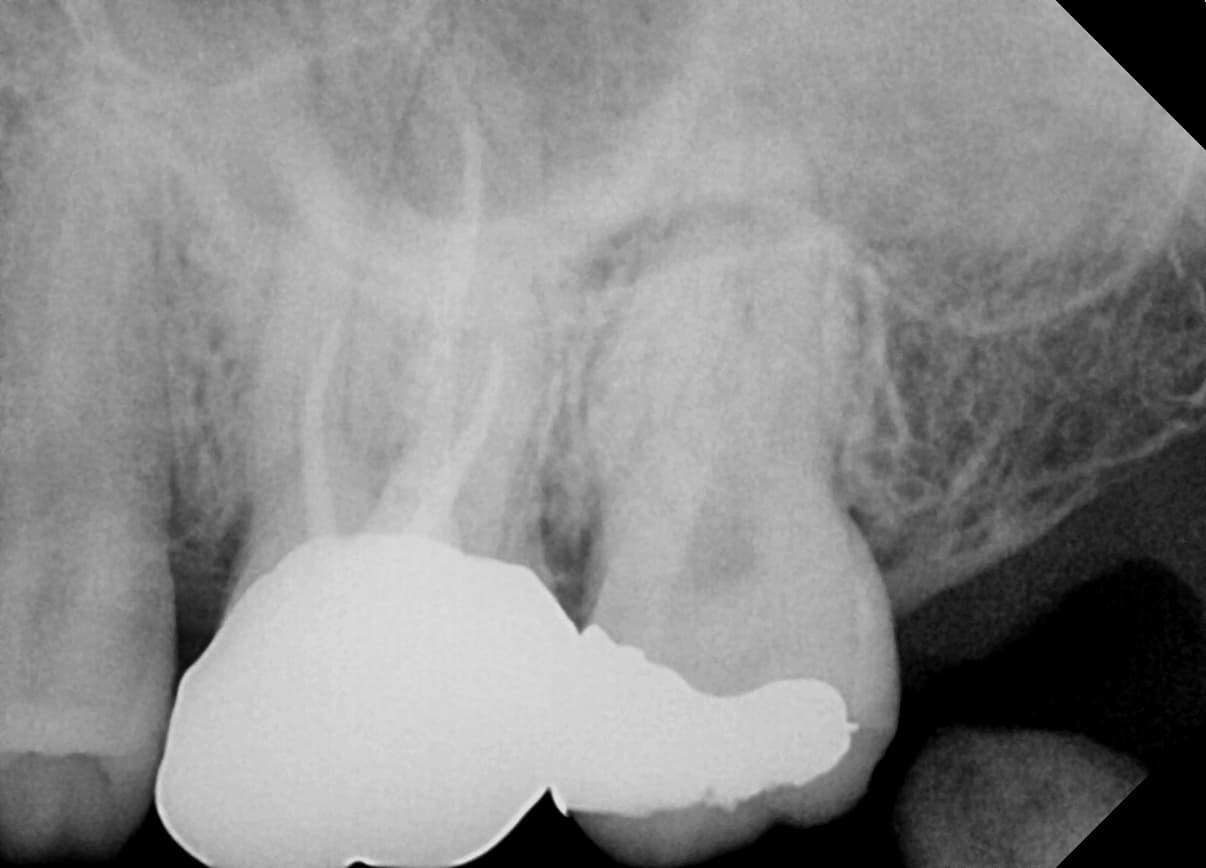

Apicoectomy

Front tooth with inflammation spreading to root tip

Before

After

Complete healing of lesion after root canal re-treatment and apicoectomy